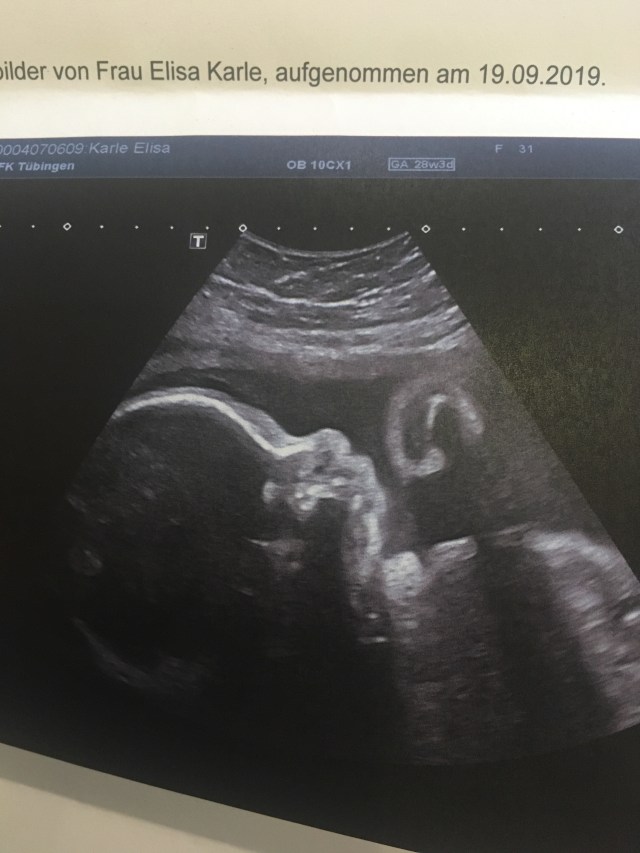

Heute morgen habe ich mich um 6 Uhr wieder auf den Weg in die Klinik gemacht und ich war froh, dass ich heute wieder gehen konnte. Ich war froh, dass wir uns ansehen konnten, wie sich Krümeline schlägt und wie es ihr geht. Inzwischen bekommt man zu dieser Uhrzeit dann im angehenden Herbst die ersten Veränderungen am Himmel mit – ein neuer Tag, eine neue Chance beginnt. Ich und mein Bauch, wir bezogen also das Wartezimmer und diesmal kam ich 20 Minuten nach dem Termin drin, also alles im Rahmen. Unserem kleinen Mädchen geht es wunderbar, sie ist nun etwa 38 cm lang, ungefähr 1300 g schwer, sitzt in mir herum und bekämpft die Ultraschallsonde. Alles ist, wie es sein soll. Das zu wissen ist mir gerade unaussprechlich viel wert. Danach machte ich mich auf ins Geschäft, meine vier Stunden waren produktiv. Nun lege ich die Beine hoch und genieße ein bisschen Ruhe.

At 6 a.m. in the morning today I made my way to the clinic again and I was quite happy about the fact that it was that time again. I was happy that I could get a check-up on her, see how the baby was doing. By now, with fall on its way, one can see the morning sky turn brighter with every minute – a new day, a new chance begins. Me and my belly, we took a seat in the waiting room and were called up 20 minutes after the actually appointment, totally alright. Our precious little girl is doing fantastic, she is about 38 cm long, weights around 1300 grams and sits there, fighting the ultrasonic probe! Everything is going very well which on this day means inexpressible much. After the appointment I drove 45 minutes to my workplace and the following four hours were very productive. Now it is time to rest on the sofa and enjoy some time by myself.